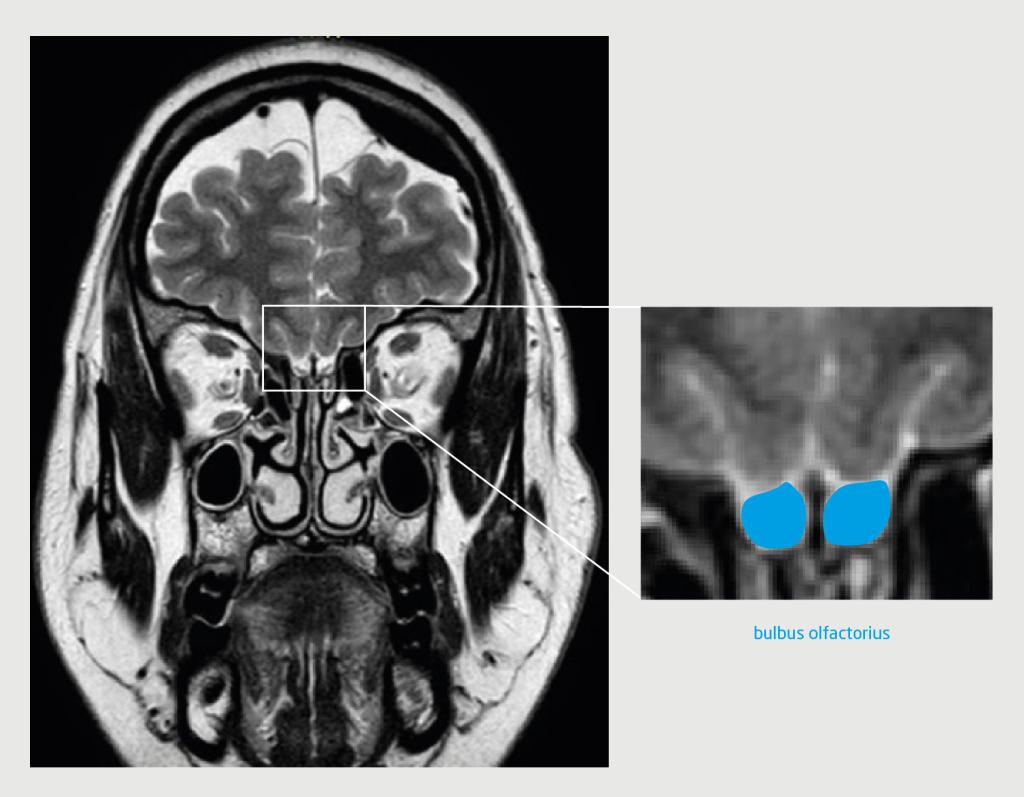

Patiënt A, een 19-jarige vrouw, kwam op de polikliniek KNO omdat ze van jongs af aan geen reukvermogen had. Zij was onderdeel van een eeneiige tweeling; haar zus kon wel goed ruiken. De reuktest liet een score zien die paste bij een afwezig reukvermogen (anosmie). Het KNO-onderzoek inclusief nasendoscopie liet een vrije middelste neusgang en reukspleet zien. We vermoedden een congenitale anosmie en verrichtten een MRI-scan. Deze liet beiderzijds een volledig afwezige bulbus olfactorius zien. De sulcus olfactorius was wel aanwezig (figuur 1).

Figuur 1 | De hersenen van de patiënte met congenitale anosmie

T2-gewogen turbospinecho-MRI van de hersenen van patiënt A (coronale coupe). Ter hoogte van de voorste schedelbasis is beiderzijds de bulbus olfactorius afwezig (witte pijl). De sulcus olfactorius (blauwe lijn) oogt beiderzijds normaal. Bij patiënten met het syndroom van Kallmann kan deze soms ook afwijkend of zelfs afwezig zijn.